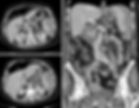

Figure 1. Contrast enhanced CT of abdomen and pelvis. How would you grade this injury? What action should be taken for this patient who is hemodynamically unstable?

Figure 2. Contrast enhanced CT of abdomen and pelvis demonstrating IV contrast extravasation from the spleen (red arrows). Note also the hematomas adjacent to the spleen and liver.

Figure 3. Initial selective splenic artery angiogram and subsequent coil embolization.

Grade IV injuries include lacerations that extend into segmental or hilar vessels and result in major devascularization of more than 25% of the spleen and any injuries with the presence of a splenic vascular injury or active bleeding within the splenic capsule. Since there is contrast extravasation, this is case is considered a Grade IV injury (Figs. 1-2). Grade V injuries are the most severe form, involving a shattered spleen or hilar vascular injury leading to devascularization of the organ and active bleeding extending beyond the spleen into the peritoneum [1]. Prompt identification of the injury grade is essential for guiding treatment decisions.